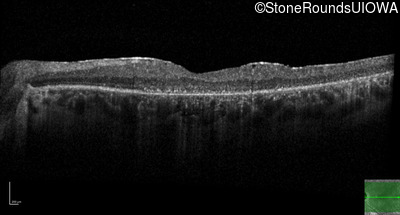

Optical Coherence Tomography - Right - 10/200

Exemplar / OCT Stack

OCT Stack